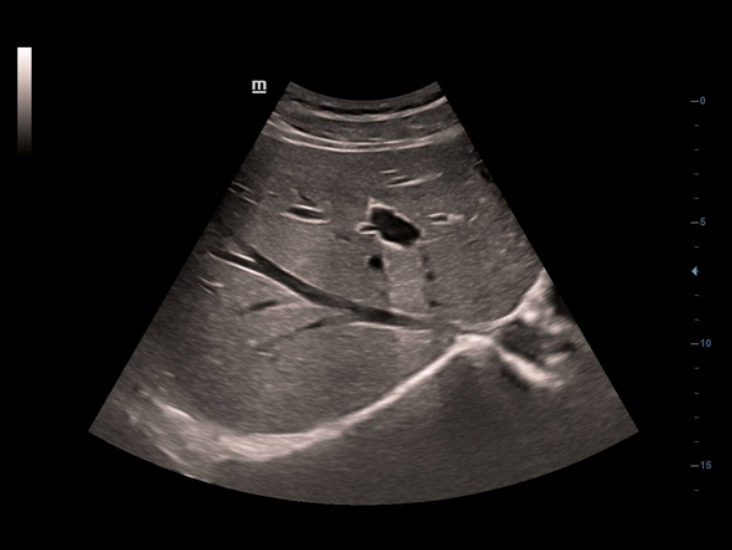

Dual-Volume

DC-40 met Full HD combineert het convexe volume, het endocavitaire volume en de bijbehorende toepassingspakketten en introduceert daarmee de Dual-Volume-oplossing, die speciale 4D-zorg voor vrouwen biedt vanaf de prenatale onderzoeken tot de zwangerschapscontrole